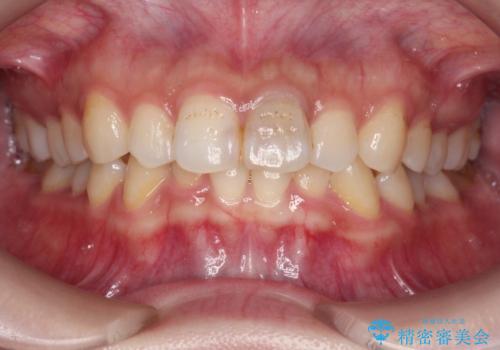

前歯のブリッジ治療

- 前歯部の歯ぐきが腫れたり、にきびのようなものが繰り返しできる。と不快症状を訴えて来院されました。

X線検査を行い診断的な小手術を行ったところ、歯に亀裂があり修復が不可能な状態であることがわかりました。

長期的な予後を見通すことが難しかったので、亀裂のある前歯の抜去を行いブリッジで審美性・機能性の回復を行いました。